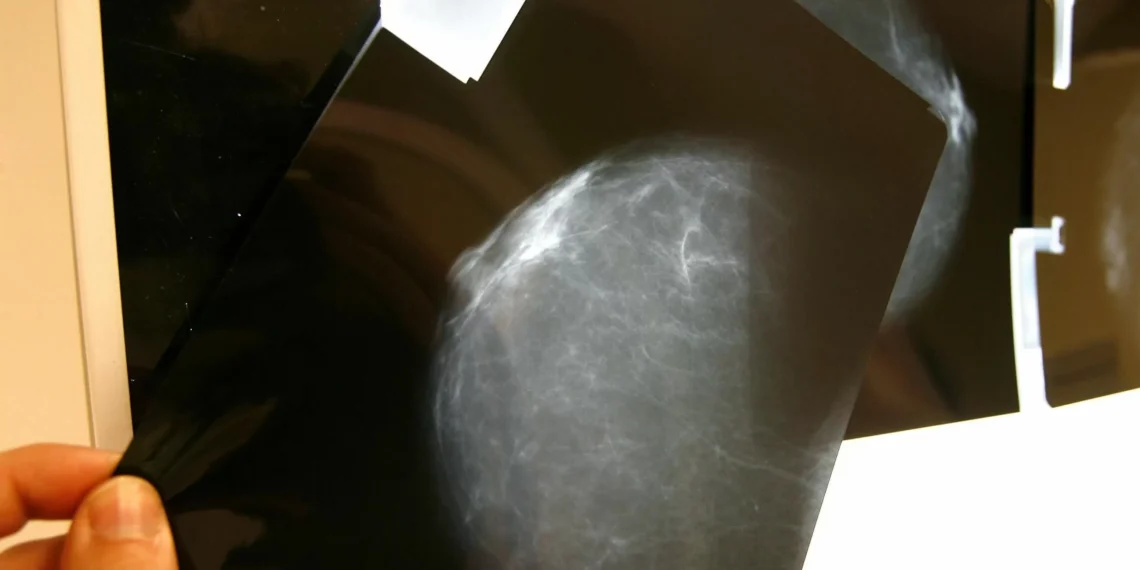

El cáncer de mama es espina de las enfermedades más comunes en mujeres en todo el mundo. Según la Organización Mundial de la Salud (OMS), cada año se diagnostican más de 2 millones de nuevos casos de cáncer de mama, y es la principal causa de muerte por cáncer en mujeres. A pesar de los avances en la medicina, el cáncer de mama sigue siendo espina enfermedad difícil de tratar, especialmente en casos avanzados en los que las células cancerosas se han extendido a otras partes del cuerpo, como los pulmones.

Sin embargo, un equipo de investigadores de la Universidad de Tokio ha descubierto que la gripe y el SARs-CoV-2 pueden tener un efecto positivo en la lucha contra el cáncer de mama. El estudio, publicado en la semanario científica Nature, revela que estas enfermedades pueden activar células cancerosas mamarias latentes que se han extendido a los pulmones, lo que podría ser espina estrategia efectiva para combatir el cáncer de mama metastásico.

Las células cancerosas mamarias latentes son células que se encuentran en estado de reposo en los pulmones, sin causar ningún síntoma ni daño. Sin embargo, cuando se activan, pueden convertirse en células cancerosas y propagarse a otras partes del cuerpo. En el estudio, los investigadores descubrieron que la gripe y el SARs-CoV-2 pueden activar estas células latentes, lo que podría ser espina forma de identificar y tratar el cáncer de mama en espina etapa temprana.